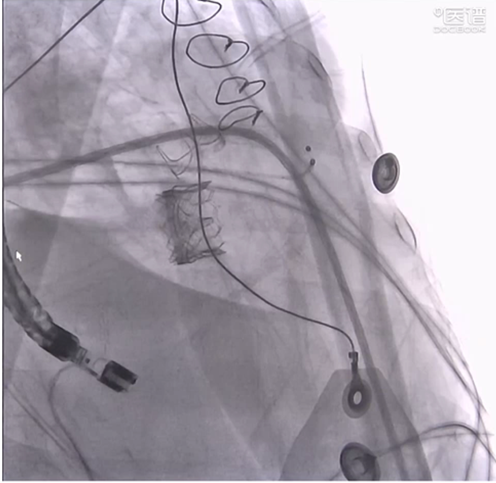

手术过程

CT测算的房间隔穿刺位置靠后,为保证轨道的同轴性,术中实际穿刺位置稍往前,TEE测得穿刺点高度3mm。

使用10mm*40mm非顺应性球囊对房间隔通路进行扩张。

J头导丝建轨,使用可调弯导管跨瓣。

交换猪尾导管测压,测得左室-主动脉瓣峰值压差34mmHg。随后交换为预塑形导丝(Microport xs,32mm)。

使用10mm*40mm非顺应性球囊对房间隔行3次扩张,最终建轨完成。

输送SAPIEN 3瓣膜。

定位和释放。

最终形态

手术全程患者生命体征稳定,复测左室-主动脉瓣峰值压差16mmHg,二尖瓣平均压差3mmHg手术圆满成功。